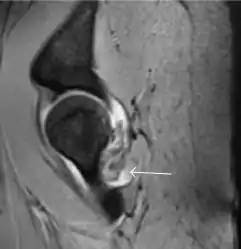

Synovial chondromatosis can be confidently diagnosed by X-ray when calcified cartilaginous chondromas are seen. However, other synovial proliferative processes, such as pigmented villonodular synovitis, require MRI for accurate diagnosis, although noncalcified synovitis can be suspected in radiographs by indirect signs, such as soft tissue swelling and/or erosions in the femoral head, femoral neck, or acetabulum (Figure 7).[1]

Figure 7:

Axial CT image of pigmented villonodular synovitis eroding the posterior cortex of the femoral neck.[1]

Sagittal T2* gradient echo image showing a posterior soft tissue mass with hypointense areas secondary to hemosiderin deposition.[1]

X-ray of synovial chondromatosis.[1]

CT of synovial chondromatosis.[1]

In synovial proliferative disorders, MRI demonstrates synovial hypertrophy. In the case of PVNS, characteristic foci of low signal intensity related to hemosiderin deposition are better seen on gradient echo T2* images (Figure 7). In the case of synovial osteochondromatosis, the synovial hypertrophy is accompanied by intermediate signal cartilaginous loose bodies and/or low signal calcified loose bodies.[1]